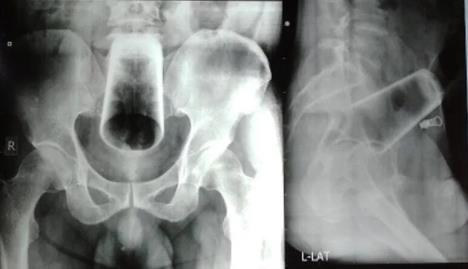

"Pacijent se žalio na bolove u stomaku i nemogućnost obavljanja velike nužde. Stomak mu nije bio natečen, nije krvario, niti je imao vidljive povrede. Međutim, rendgenski snimak pokazao je da u anusu ima 12 centimetara dugačku staklenu čašu. Hirurzi su prvo pokušali da ručno izvade predmet, ali je on bio čvrsto i duboko zaglavljen u rektumu. Medicinsko osoblje nije smelo da ga izvuče na silu jer je postojao veliki rizik da će se čaša polomiti i da će staklo povrediti debelo crevo pacijenta", piše u članku objavljenom u "Žurnalu nepalske medicinske asocijacije", u kom se ne navodi kad se ovaj bizaran slučaj dogodio.

Kako nije bilo druge opcije, odlučeno je da pacijent bude operisan i da mu čaša hirurškim putem bude izvađena kroz stomak.